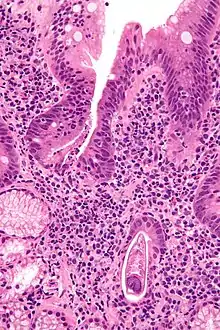

Micrograph showing strongyloidiasis; a fragment of a worm is seen in the lower right hand corner. H&E stain.